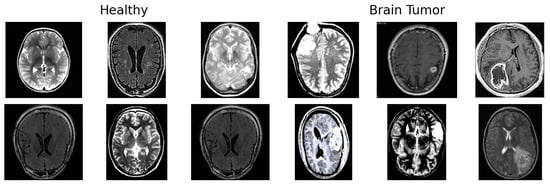

The dataset includes a total of 3000 labeled MRI images, evenly split into two diagnostic categories (Figure 2):

• 1500 Healthy brain images (no signs of tumor).

• 1500 Brain Tumor images (showing tumors of various types and sizes).

These images represent the essential material for training models to detect and differentiate between healthy and tumorous brain tissue. Since the manual analysis of such complex medical images can be error-prone, the dataset supports the use of automated techniques for improved accuracy and reproducibility.

Figure 2. Example images from the two classes in the dataset: Brain Tumor and Healthy.